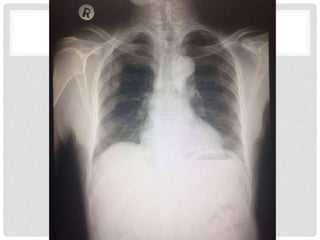

ผู้ป่วยชายไทย อายุ 78 ปี

No underlying disease

CC : ปวดไหล่ขวา 5 วันก่อนมาโรงพยาบาล

E : 5 วันก่อนมาโรงพยาบาล ขี่จักรยาน ล้มเอง ไหล่ขวากระแทกพื้น เจ็บไหล่

ขวา ยังขยับได้ แต่ยกแขนได้ไม่สุด ไหล่ขวาบวมมากขึ้น เริ่มยกแขนลาบาก กินยา

แก้ปวดที่บ้าน อาการไม่ดีขึ้น จึงมาโรงพยาบาล